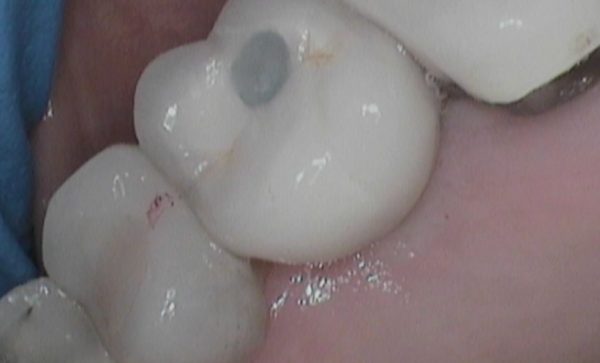

Case 47